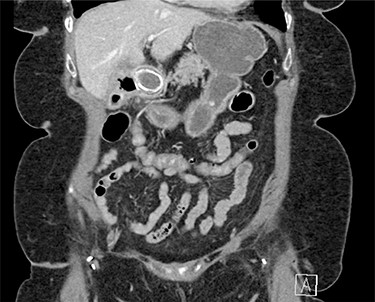

On physical exam, patient was tender in the epigastrium and right upper quadrant with no abdominal distension or peritoneal signs. Initial laboratory studies revealed white blood cell count: 8.83 K/mcl, international normalized ratio: 2.2, aspartate aminotransferase: 22 U/l, alanine aminotransferase: 19 U/l, total bilirubin 0.5 mg/dl and direct bilirubin: 0.1 mg/dl. Computed tomography (CT) scan of abdomen and pelvis showed pneumobilia with a cholecystoduodenal fistula and a large gallstone causing gastric distension proximally with no small bowel dilatation distally (Figs 1 and 2).

Abdominal CT scan (coronal plane) with the large impacted gallstone causing gastric outlet obstruction proximally with no small bowel dilation distally.